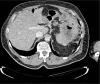

Diagnoses: After 3 months of therapy, a computed tomography scan showed an impressive reduction of disease.